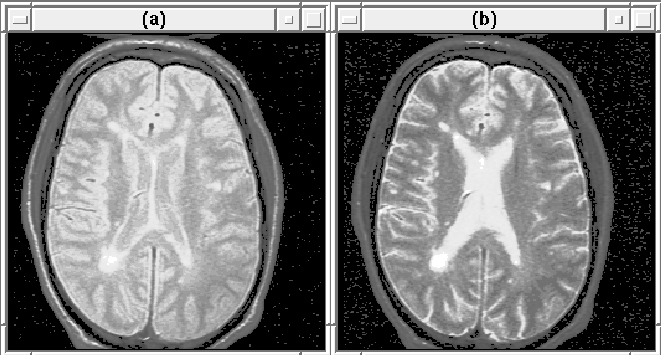

The MR images used in this thesis were all acquired using a Multiple Echo Spin Echo pulse sequence in which two images are

acquired simultaneously.

and

are adjusted such that

tissues with a high proton density appear bright in the first image

and tissues with a long

appear bright in the second image. The

two images are said to be proton density-weighted (PD-weighted) and

T2-weighted respectively. Figure 2.3 shows 2D slices

from the weighted MRI volumes.

Figure 2.3: (a) A proton density (PD) weighted MR image

slice. (b) The same T2-weighted slice.